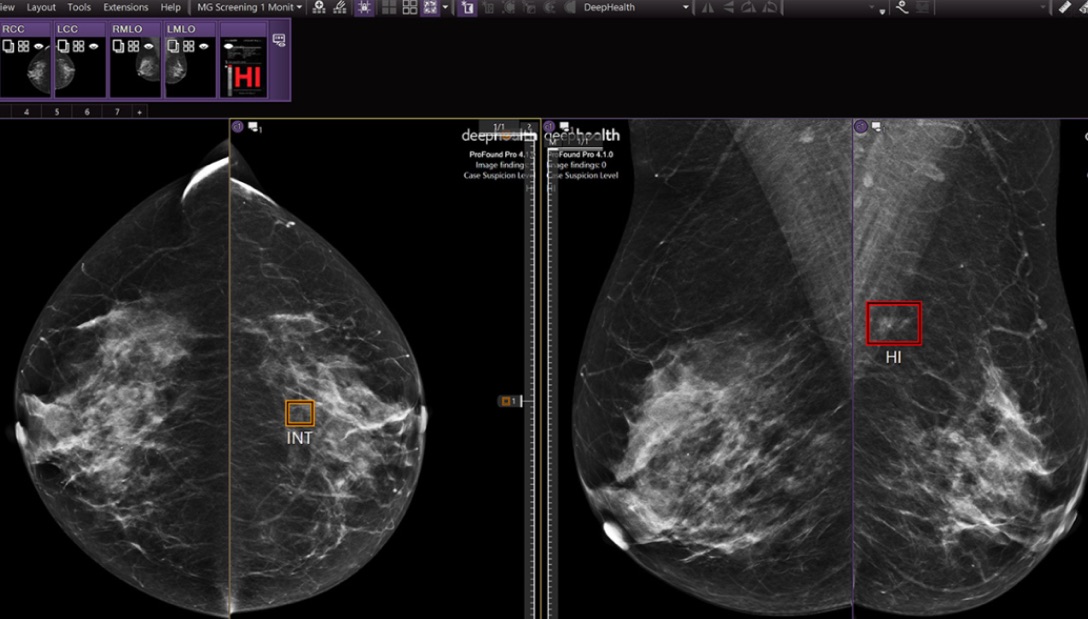

Enables more accurate diagnosis1,2 with the use of priors3 and automatic localization of regions of interest and degree of suspicion

Improves turnaround time by indicating cases based on suspicion level and rapidly flagging high-suspicion exams within minutes, reducing delays and enabling timely same-day follow-up.

AI-powered Safeguard review workflow

Improves cancer detection rate with second reviewer workflow, decreasing false negatives and emphasizing likely missed cancers, including hard-to-detect ones. 2, 7, 8